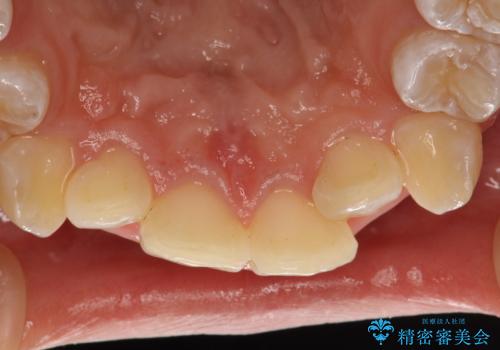

- 矯正治療前にステインを取りたいとのことで来院されました。ステインは前歯のみだったため、PMTC30分コースを行いました。

PMTCとは、歯科の専門家が器械を使用して行う歯のクリーニングのことです。普段の歯磨きでは取り切れない溝、キワなどの細かい部分も徹底的に除去します。ステインや歯石などが付着したままだと、虫歯や歯周病の発見がしずらいことがあります。特に矯正治療前には、念入りな虫歯や歯周病チェックが必要なため、PMTCでしっかりと汚れを除去しておくことが大切です。